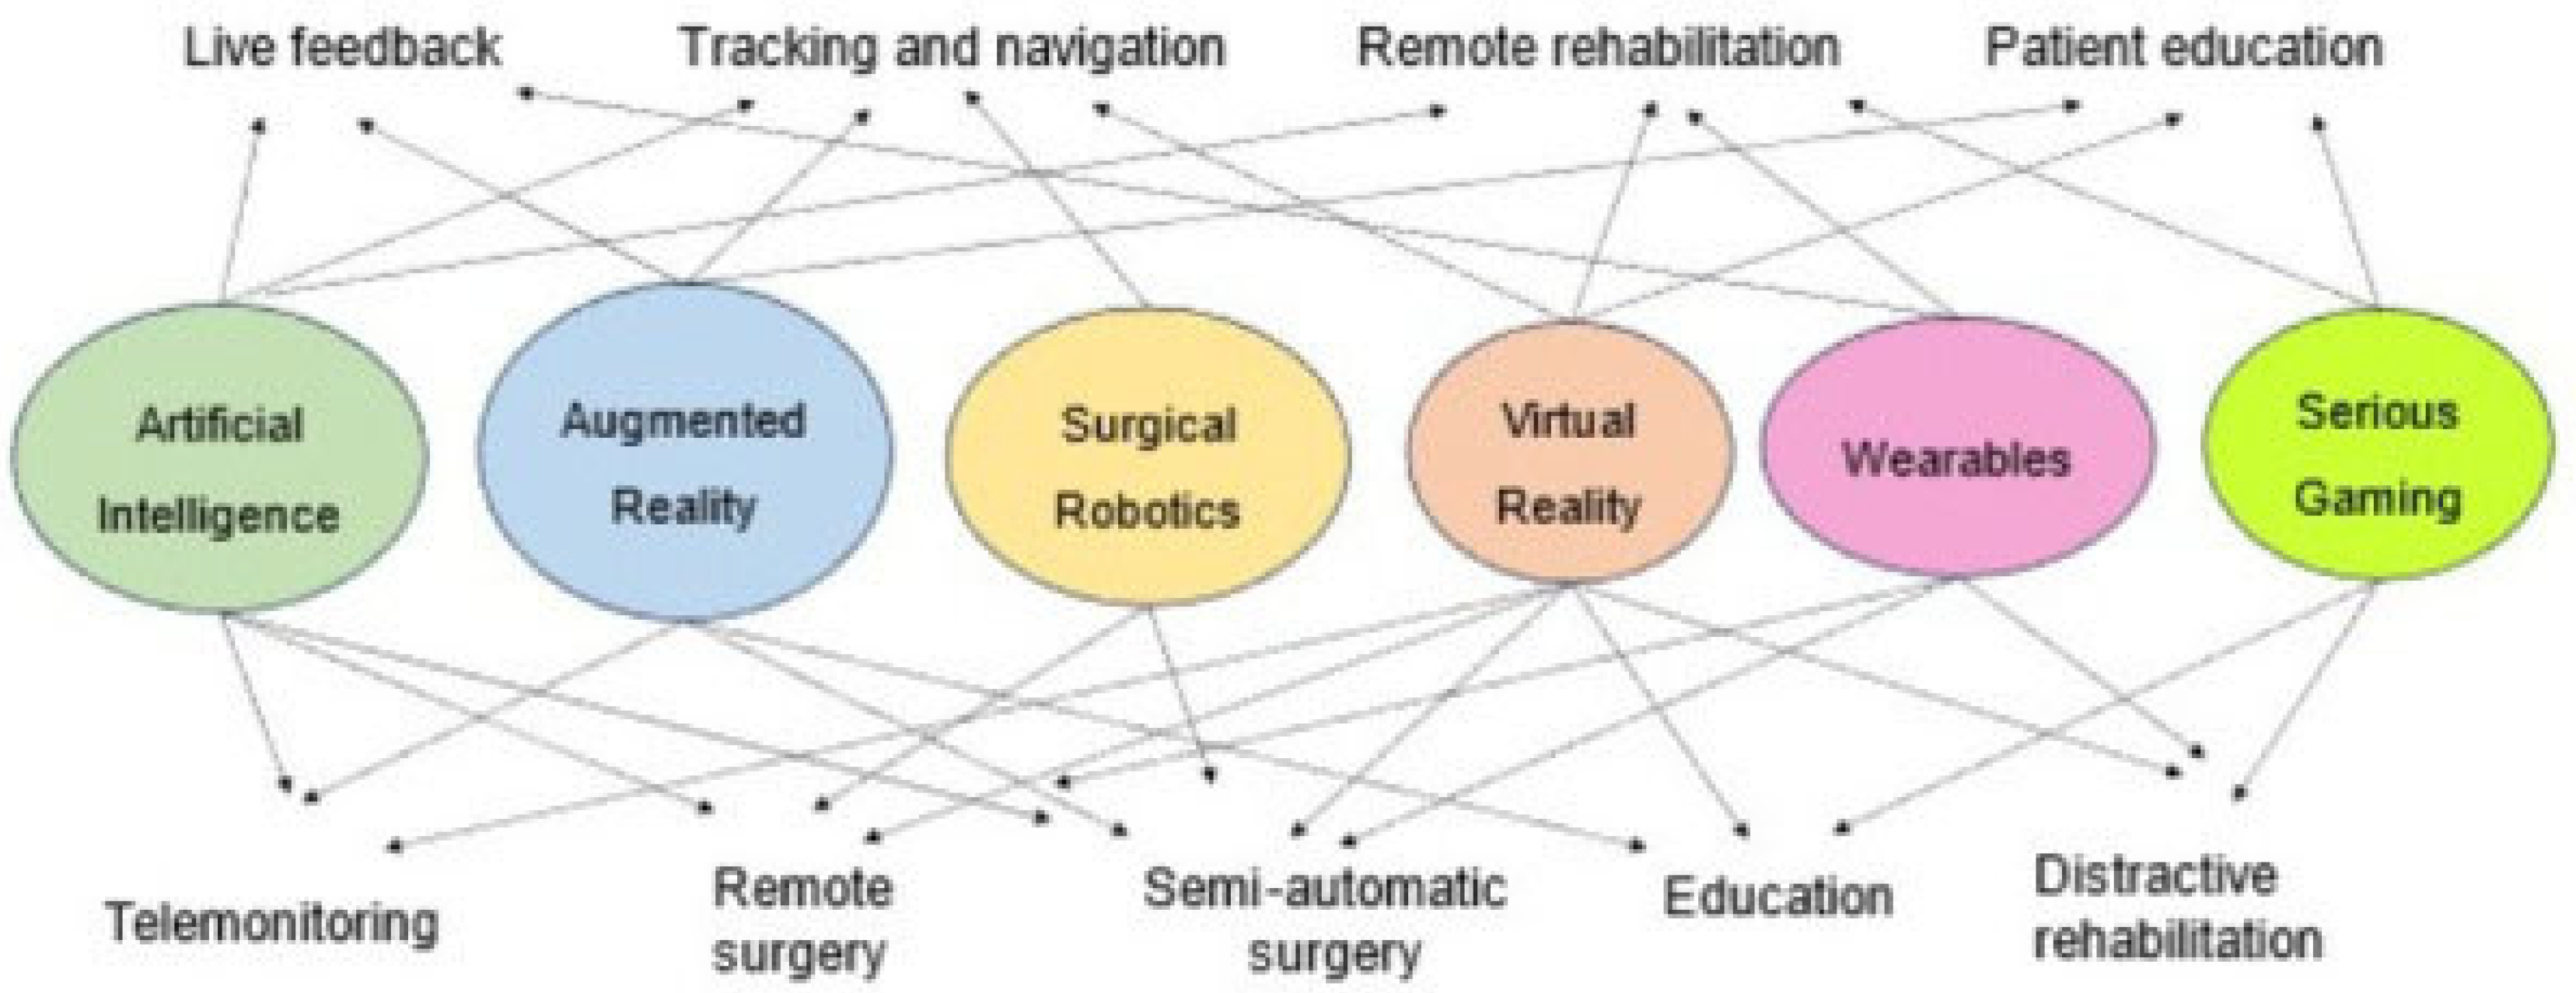

Surgical simulation is an increasingly valuable educational tool, offering trainees the opportunity to practice in a safe, standardized, and controlled environment. A recent study highlights the strong educational potential of Virtual Reality (VR) in spine surgery training, particularly for early-stage trainees [

51]. Results showed notable improvement in anatomical knowledge, especially among junior trainees, with an 11.4% average increase in post-test scores. When combined with immersive technologies, such as Augmented Reality (AR) and VR, AI can even further elevate surgical education in pediatric spine care. The synergistic integration of AI, VR, and AR into emerging healthcare technologies holds immense potential to transform how surgeons learn, plan, and operate [

52]. (

Figure 10) Future studies could explore more into the potential of their integration.